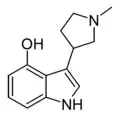

MPMI[26] | 3-[(1-methylpyrrolidin-2-yl)methyl]-1H-indole | 143321-54-4 |

|

Lucigenol | (R)-3-(N-methylpyrrolidin-2-ylmethyl)-4-hydoxyindole | 250672-65-2 |

|